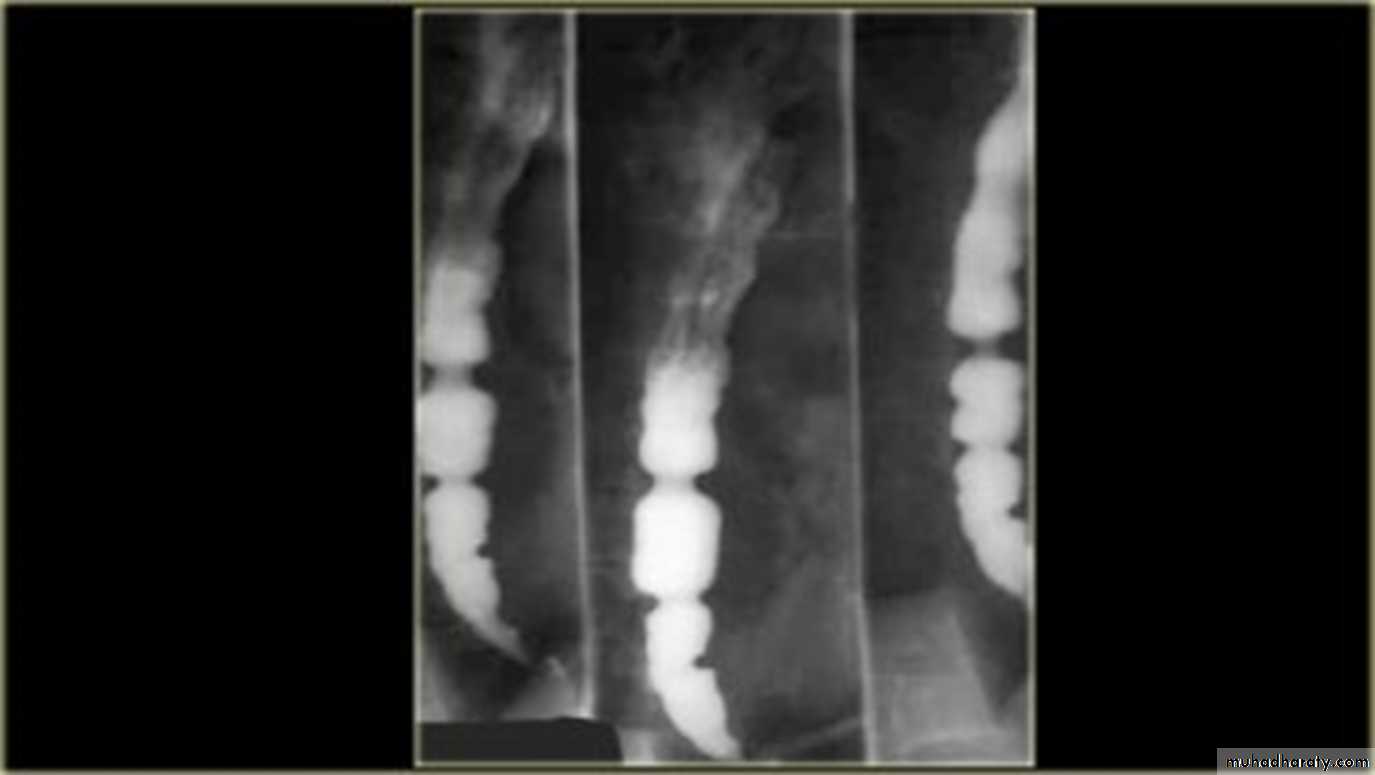

On the Hypo pharyngeal part Common structures that we can visualize are:

EpiglottisPost cricoid impression

Crico pharyngeal muscle impression

lateral pharyngeal pouches

LEFT: Lateral view: Epiglottis (red arrow).

Post cricoid impression (yellow arrows).Crico pharyngeous impression (white arrow).RIGHT: AP-view: Small lateral pharyngeal pouches (arrows)